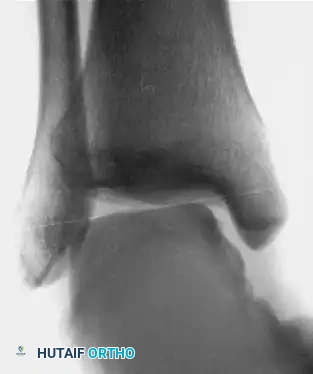

Associated Surgical & Radiographic Imaging